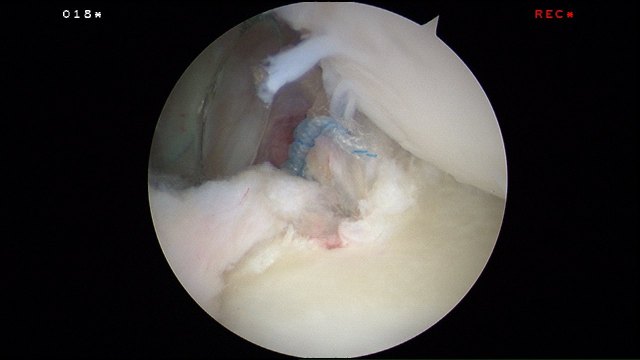

The sutures are passed around the labral tear using a shuttle suture (blue).

The suture is looped around the torn labrum and ready for tying.